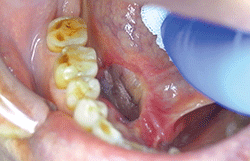

全身麻酔下にて、右口底部悪性唾液腺腫瘍切除術と植皮術を施行した(図❹)。その後、放射線治療(66グレイ)を実施した。後日、転移性肝癌(腺様嚢胞癌)となり、近医総合病院腫瘍内科にて化学療法を開始した。

図❹ 術中